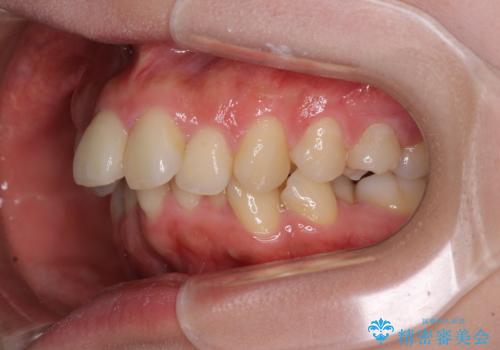

全顎的なデコボコと口元の突出感 ワイヤー装置での抜歯矯正で整った口元に

- 奥歯も含めて全体的なデコボコと前歯の突出感を気にして来院された患者様です。

上下左右第一小臼歯4本を抜歯し、ワイヤー装置にて矯正治療を行うこととしました。

前歯の突出感がなくなり、仕上がりには大変満足していただけました。